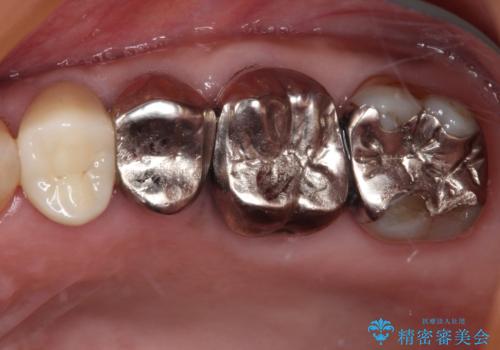

外見からはあまり大きな虫歯があるようには見えなくても、X線検査をすることで、詰め物の下に虫歯が広がっていることは多々あります。

定期的に歯科医院を受診し、早期発見・早期治療をすることで、歯の神経を残す治療が可能になります。